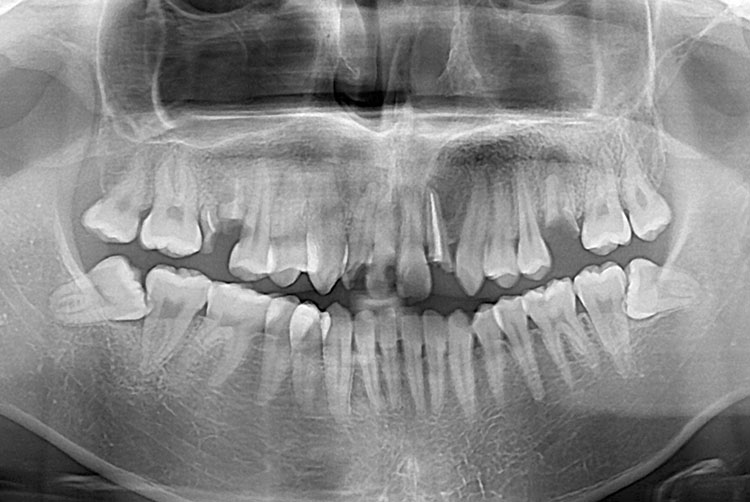

[임플란트] 임플란트

치료전 : 2015-06-11